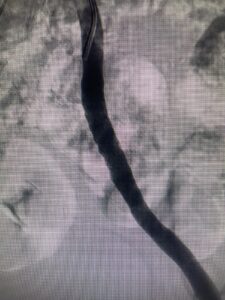

- Nuevo caso de endofibrosis ilíaca externa en ciclista profesional